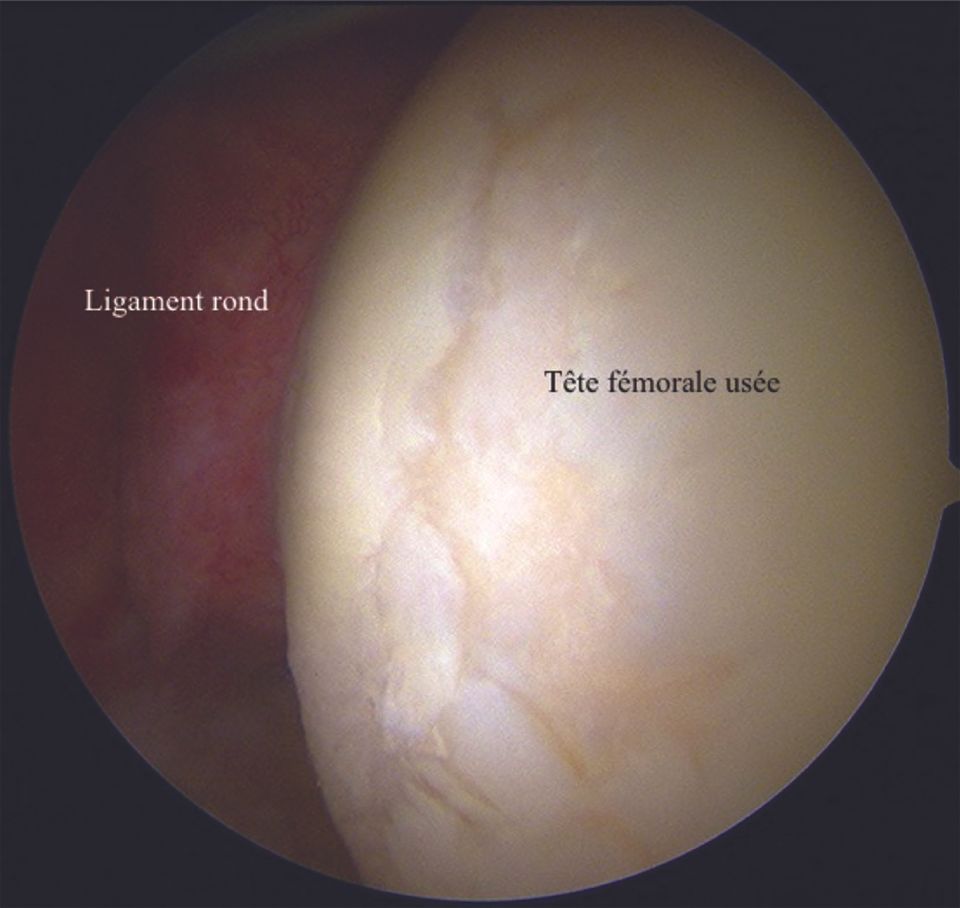

6. Femoral head view

This view enables the exploration of a large part, but not all, of the cartilage of the femoral head (Fig. 12).